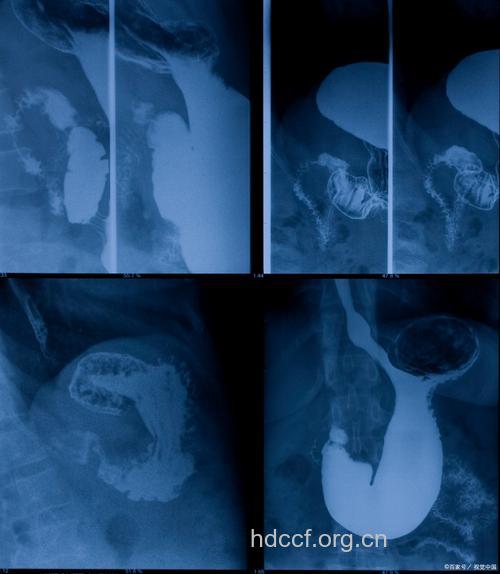

X线检查对胃癌的诊断依然有较大的价值。

气钡双重对比法、压迫法和低张造影技术,并采用高密度钡粉,能清楚地显示黏膜的精细结构,有利于发现微小的病变。

气钡双对比造影改变了传统上消化道造影法,对1~2cm 的黏膜癌也能发现。